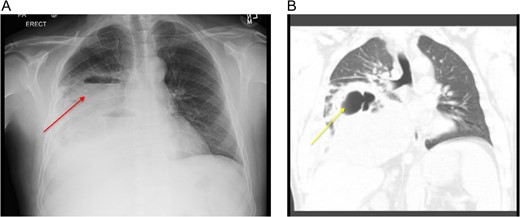

We report a case of 48-year-old Caucasian non-smoking male, admitted to the chest service for worsening pneumonia-like symptoms for the past 3 weeks (generalized malaise, productive cough and intermittent fevers and chills) despite receiving intravenous antibiotics. Chest examination revealed significant expiratory wheezing and crackles at the right lung base. The admission chest x-ray (Fig. 1A) which was subsequently confirmed with a computed tomography (CT) scan showed a large right hydropneumothorax of the right lower lung lobe (Fig. 1B). He had no history of exposure to asbestosis or tobacco products. However, 5 years ago, the patient experienced similar symptoms with a homogeneous CT scan for which he underwent a video-assisted thoracoscopic surgery (VATS) with partial decortication, for what they diagnosed to be an empyema. Based on his history and CT findings, the potential diagnosis of recurrent empyema emerged. He was thus started on broad-spectrum antibiotics and prepared for decortication the next day.

(A) CXR showing a large loculated right hydropneumothorax of the right lower lung lobe. (B) Computed tomography scan showing a large loculated right hydropneumothorax of the right lower lung lobe.